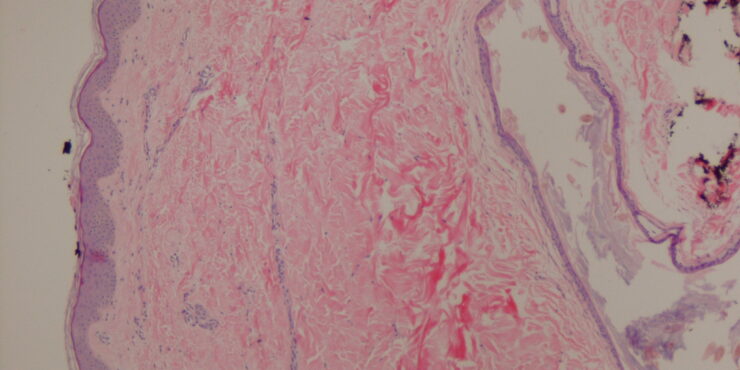

Read MoreVerrucous hemangioma = الوعاؤوم الدموي المتثألل